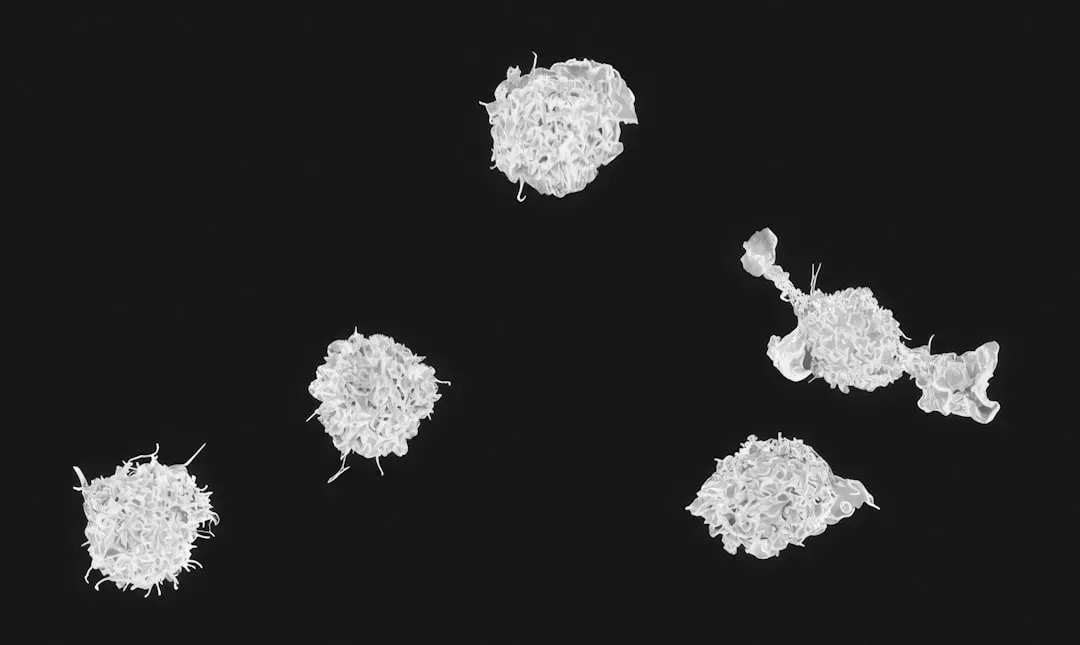

3. White Blood Cells: Your Internal Army on Patrol

White blood cells are the key players in your immune system. They are made in your bone marrow and are part of the lymphatic system. White blood cells move through blood and tissue throughout your body, looking for foreign invaders such as bacteria, viruses, parasites and fungi. Imagine billions of tiny soldiers endlessly patrolling every highway and back road of your body, every single second of the day.

Bacteria or viruses that enter the body can be stopped right away by phagocytes, also known as scavenger cells. These special white blood cells enclose germs and “digest” them, making them harmless. The remains of the germs move to the surface of the phagocytes, where they can be detected by the adaptive immune system. That last part is crucial. It’s not just about killing the immediate threat. Your body is also learning from every attack, building intelligence for future battles.

If, for example, an area of skin becomes infected, immune system cells spring into action, either by moving to the area or by being activated locally. Certain cells of the immune system release substances to make the blood vessels wider and more “leaky,” causing the area around the infection to swell, become warm and turn red, which are visible signs of inflammation. That redness and swelling you see on a cut? That’s not a failure. It’s your army mobilizing at speed.